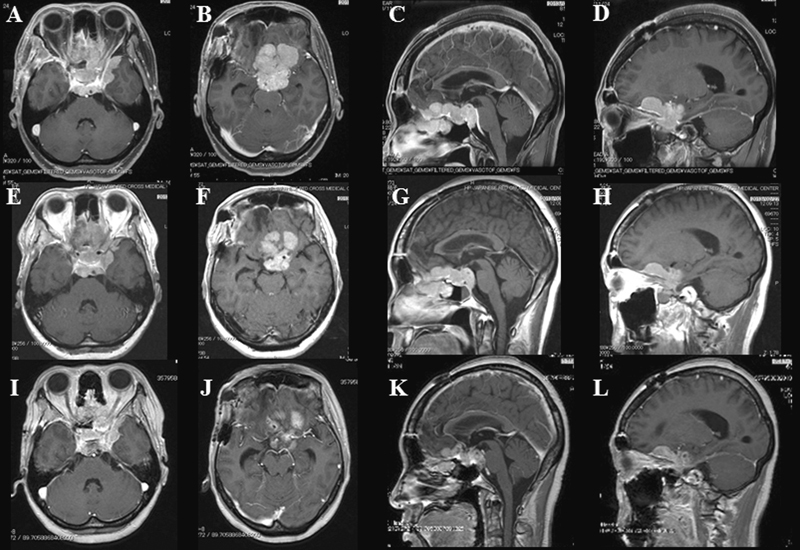

在观察过程中,所有前颅底脑膜瘤患者的肿块均显示体积缩小。尽管所有肿瘤均表现出逐渐缩小的趋势,但在某些患者中,BNCT治疗后通常观察到短暂的增加,通常是在放疗后一个月内,然后再次减少。这种模式称为伪渐进(图1)。图2代表肿瘤缩小的说明性情况。该患者是一名49岁的女性,前颅底发育为非典型脑膜瘤。BNCT治疗后3个月,患者的体积减少了30%。

图2:BNCT治疗之前(A–D),治疗之后(E–H)3周和治疗之后3个月(I–L)的非典型脑膜瘤的图像。